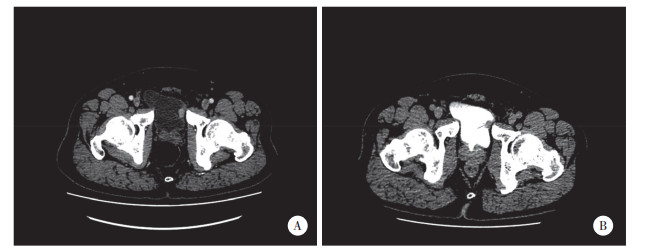

本次入院膀胱镜检查发现膀胱左侧壁1枚乳头样肿物,见图 1。CTU检查显示:膀胱左侧壁局限性增厚,平扫CT值约50 HU,增强扫描可见强化结节,直径约1.5 cm,基底较宽,CT值约74 HU,延迟期局部略充盈缺损,见图 2。泌尿系统彩色多普勒超声显示:膀胱左侧壁1处隆起样回声,大小约1.73 cm×1.27 cm,形态不规则,膀胱壁欠光滑。头部及肺部CT、肝胆脾超声、尿常规等检查均未见明显异常。术前诊断:膀胱恶性肿瘤。全身麻醉下行膀胱部分切除术。术后病理诊断:LELC (侵及肌层)。免疫组织化学结果:CK20 (-),CD30 (-),P63 (+),GATA-3(+),CD45 (LCA) (+),CD15 (散在+),P53 (散在+),CK (部分+),CK7 (部分+),Ki-67 (约50%+),CD3 (T细胞+),CD20 (B细胞+),HE染色切片见图 3。结合术前检查结果和术后病理结果最终诊断为膀胱淋巴上皮瘤样癌(lymphoepithelioma-like carcinoma of the bladder,LELCB),临床病理分期:pT2N0M0。术后1个月开始行多西他赛联合顺铂(DP方案) 辅助化疗。术后随访15个月,患者一般状态良好,无肿瘤复发和转移迹象。本研究已获得患者知情同意。

| A,动脉期;B,延迟期. 图 2 术前CTU检查见膀胱左侧壁软组织肿块 |

本病例术前CTU检查发现肿瘤基底部膀胱壁增厚,考虑可能有肌层浸润,故采用膀胱部分切除术,术后病理诊断为伴有肌层浸润的LELCB,免疫组化结果CK20 (-),CK7 (部分+),GATA3 (+),并伴有淋巴细胞浸润,该结果符合LELCB的组织学特征。由于LELCB对化疗比较敏感,该患者术后采用多西他赛联合顺铂的全身化疗方案,术后随访观察15个月,无肉眼血尿发生,未见肿瘤复发和转移迹象。由于该肿瘤的特殊性,早期诊断和外科手术联合辅助治疗至关重要。